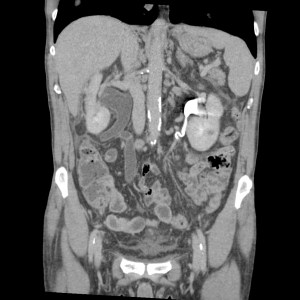

Paciente de 59 años con antecedentes personales de Cá de vejiga.

Se le realiza una Uro-Tc por seguimiento al año, aunque en esta ocasión el paciente refiere episodio de hematuria.

Tras el tratamiento de la recidiva y nefrostomía para la hidroureteronefrosis, vuelve acudir al hospital a los 9 meses por episodio de dolor en FD y malestar general. Se realiza una ecografía de urgencias.

Se realiza nueva TC bifásico abdominopélvio y Uro TC.

- Paciente con numerosas recidivas por Cá vejiga.

- Ha desarrollado un tumor metacrónico en pelvis renal derecha, también responsable de la hidroureteronefrosis.

- Mala evolución radiológica del proceso a expensas de metástasis pulmonares y hepáticas.